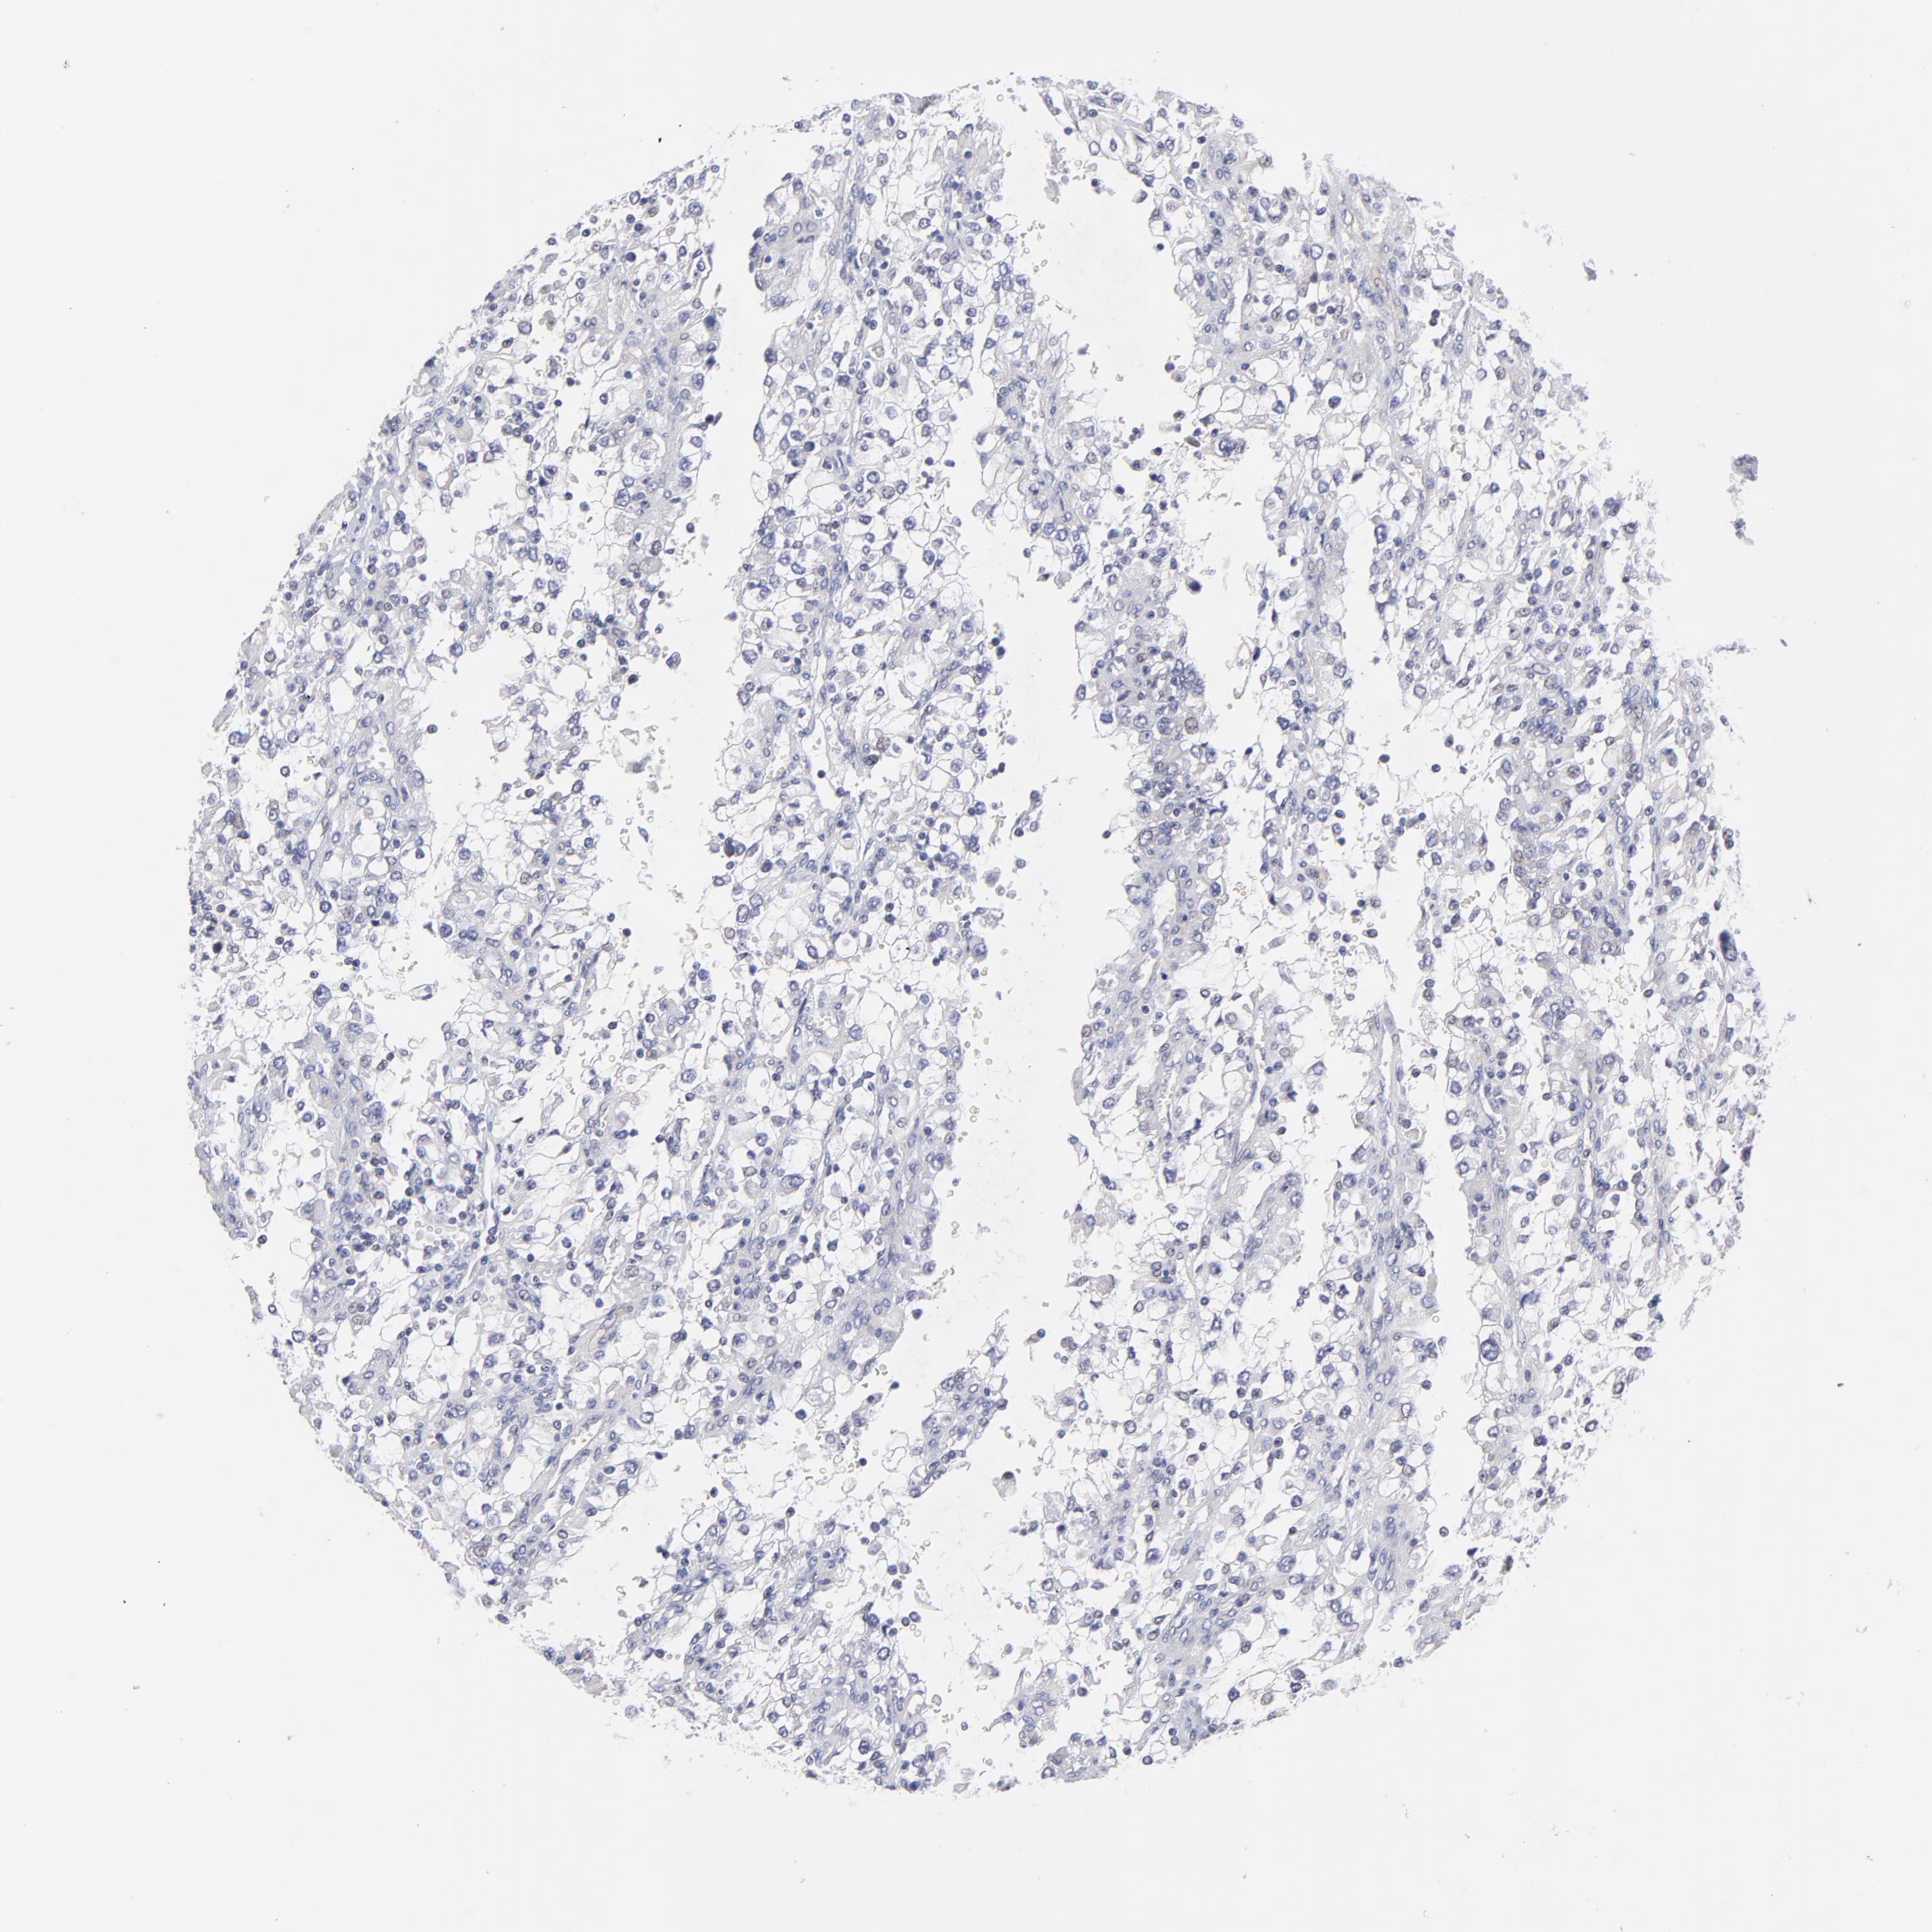

KIDNEY RENAL CLEAR CELL CARCINOMA (VALIDATION) - Interactive survival scatter ploti

The Survival Scatter plot shows the clinical status (i.e. dead or alive) for all individuals in the patient cohort, based on the same data that underlies the corresponding Kaplan-Meier plots. Patients that are alive at last time for follow-up are shown in blue and patients who have died during the study are shown in red.

The x-axis shows the expression levels (FPKM) of the investigated gene in the tumor tissue at the time of diagnosis. The y-axis shows the follow-up time after diagnosis (years). Both axes are complimented with kernel density curves demonstrating the data density over the axes. The top density plot shows the expression levels (FPKM) distribution among dead (red) and alive patients (blue). The right density plot shows the data density of the survived years of dead patients with high and low expression levels respectively, stratified using the cutoff indicated by the vertical dashed line through the Survival Scatter plot. This cutoff is automatically defined based on the FPKM cutoff that minimizes the p-score. The cutoff can be changed by dragging the vertical line or by entering a cutoff value in the square labeled "Current cut-off".

Under the Survival Scatter plot the p-score landscape (black curve; left axis) is shown together with dead median separation (red curve; right axis). Dead median separation is the difference in median mRNA expression between patients who have died with high and low expression, respectively. It is calculated as follows: median FPKM expression of dead patients with high expression - median FPKM expression of dead patients with low expression. This is intended to aid the user in visually exploring custom cutoffs and the associated p-scores and dead median separation.

Individual patient data is displayed and can be filtered by clicking on one or more of the category buttons on the top of the page. Categories describing expression level and patient information include: high, low, alive, dead, female, male and tumor stages. The scale of the x-axis can be toggled between linear and log-scale by clicking on the "x log" button. Mouse-over function shows TCGA ID, patient information and mRNA expression (FPKM) for each patient.

& Survival analysisi

Kaplan-Meier plots summarize results from analysis of correlation between mRNA expression level and patient survival. Patients were divided based on level of expression into one of the two groups "low" (under cut off) or "high" (over cut off). X-axis shows time for survival (years) and y-axis shows the probability of survival, where 1.0 corresponds to 100 percent.

FBXO8 is validated prognostic, high expression is favorable in Kidney Renal Clear Cell Carcinoma (validation)

Best expression cut offi

Based on the FPKM value of each gene, patients were classified into two groups and association between prognosis (survival) and gene expression (FPKM) was examined. The best expression cut-off refers the FPKM value that yields maximal difference with regard to survival between the two groups at the lowest log-rank P-value. Best expression cut-off was selected based on survival analysis .

When clicking on this number, the vertical dashed line indicating cut-off, the interactive survival plot, and the Kaplan-Meier curve will be adjusted to show results based on the best expression cut-off.

: 21.74

Average pTPM 20.8

Number of samples 100